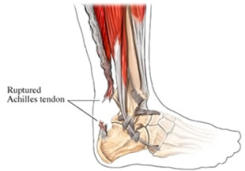

Roturas

del

tendón

de

Aquiles

Cuando

el

tendón

de

Aquiles

se

rompe

lo

hace

frecuentemente

de

forma

completa

y

brusca.

Lo

más

frecuente

es

que

el

paciente,

casi

siempre

deportista,

note

un

dolor

fuerte

y

agudo,

con

la

sensación

de

que

alguien

le

hubiera

pegado

una

patada.

A

veces

se

escucha

el

desgarro

del

tendón.

A

partir

de

ese

momento

no

se

puede

continuar

con la actividad ni apenas caminar.